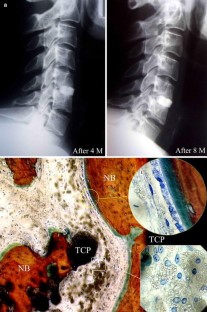

Few histological studies on bone substitutes in human cervical spine are available and the biological processes of bone substitutes are not well documented. The authors studied four failure cases of cervical interbody fusion: two cases with hydroxyapatite (HA), one case with β-tricalcium phosphate ceramic (β-TCP) and one case with xenograft (bovine bone). Clinical data showed that all the patients experienced neck pain with or without numbness of upper extremity due to fusion failure. Successful fusions were achieved after the salvage surgeries in which autograft were used. Radiographs showed that radiolucent lines were present in all cases. Two HA substitutes fractured without complications. One of them sank into the vertebral body. Some small β-TCP fragments were found under the microscope. Histological study demonstrated only a few newly formed bones at the interface of the substitutes. The fragments of HA were encapsulated by fibrous tissue. The degradation process and bone regeneration were more active in β-TCP than in HA. The intertrabecular spaces of bovine bone were filled with fibrous tissue. The results suggest that a porous calcium phosphate ceramic with special design might assure bone ingrowth and meet the mechanical requirements in cervical interbody fusion. The complications of these materials in the cervical spine should be highlighted.

Fig. 1